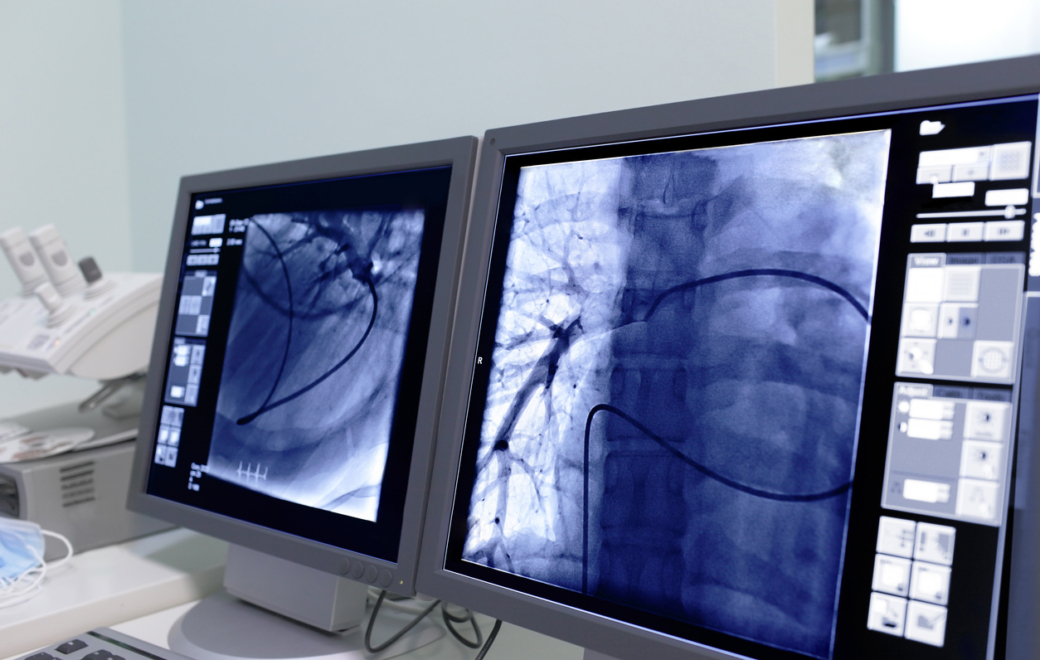

© Getty Images

Rétro 2024 : produits de contraste, chronique de ratés en série

En 2024, les produits de contraste ont officiellement été retirés du monopole pharmaceutique, conformément à un arrêté ministériel. Cela signifie qu’ils ne sont plus remboursés par l’Assurance maladie, leur coût étant désormais intégré aux forfaits techniques des radiologues qui les délivrent eux-mêmes.